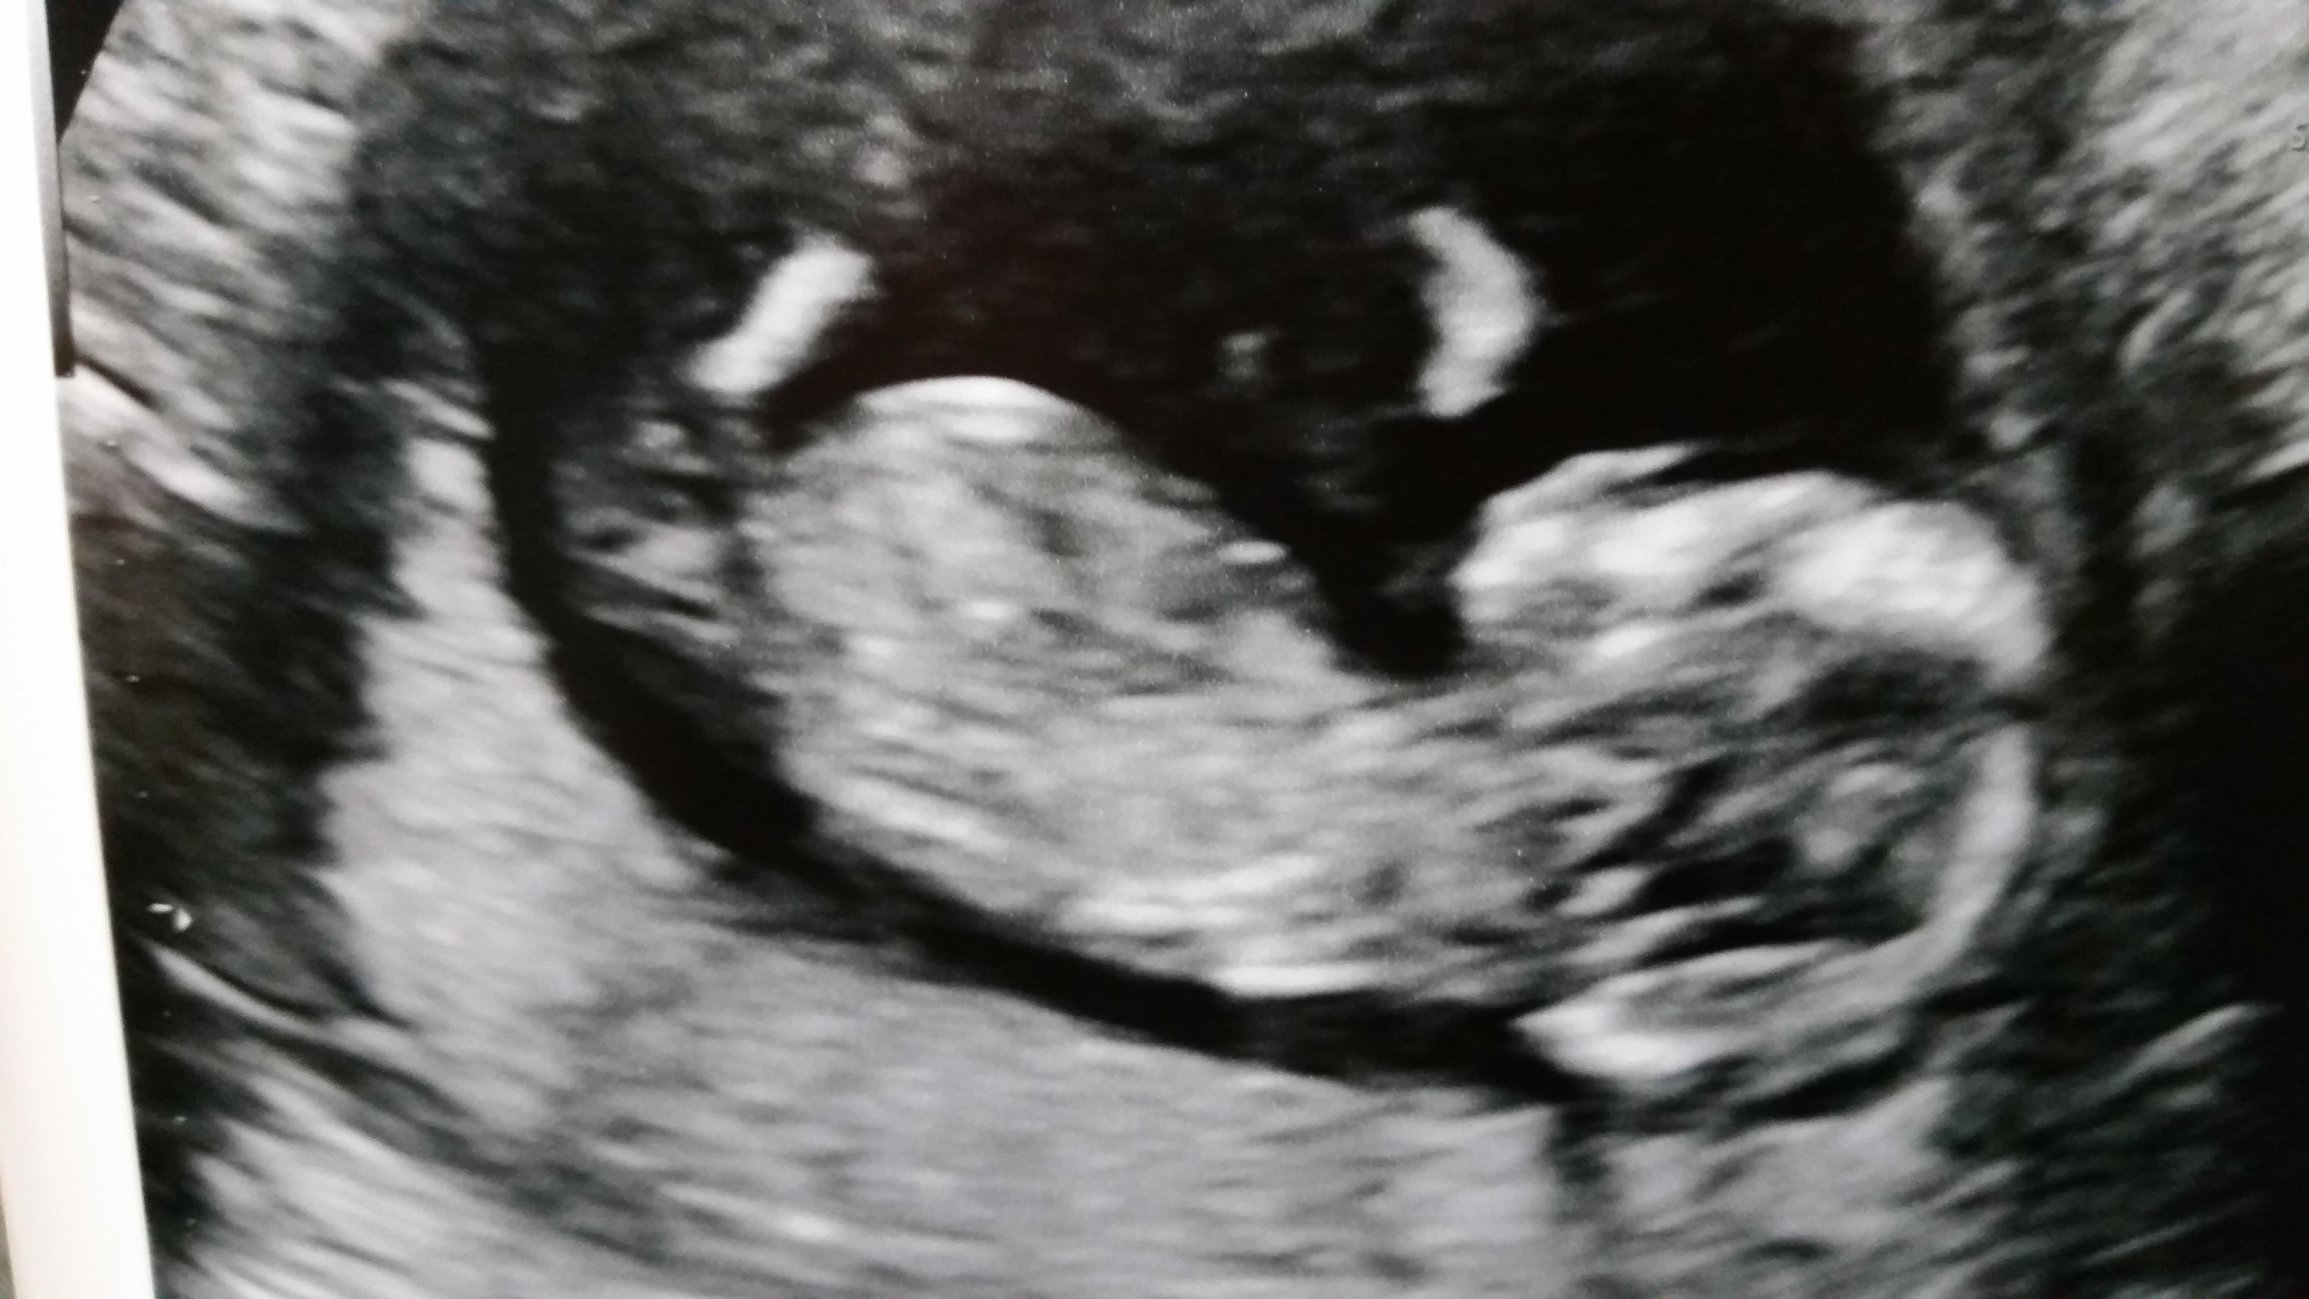

12w2d today and had my NT scan this morning! The tech told me all measurements are normal but they need to be compared with my bloodwork today to draw any conclusions. Fingers crossed everything comes back normal!! I should know by next Monday at the latest. The baby was a very active baby and made me laugh a few times. I really don't think the baby likes the ultrasound machine. I have my anatomy scan scheduled for 3/16, which is exciting!

Here's a picture of my baby!